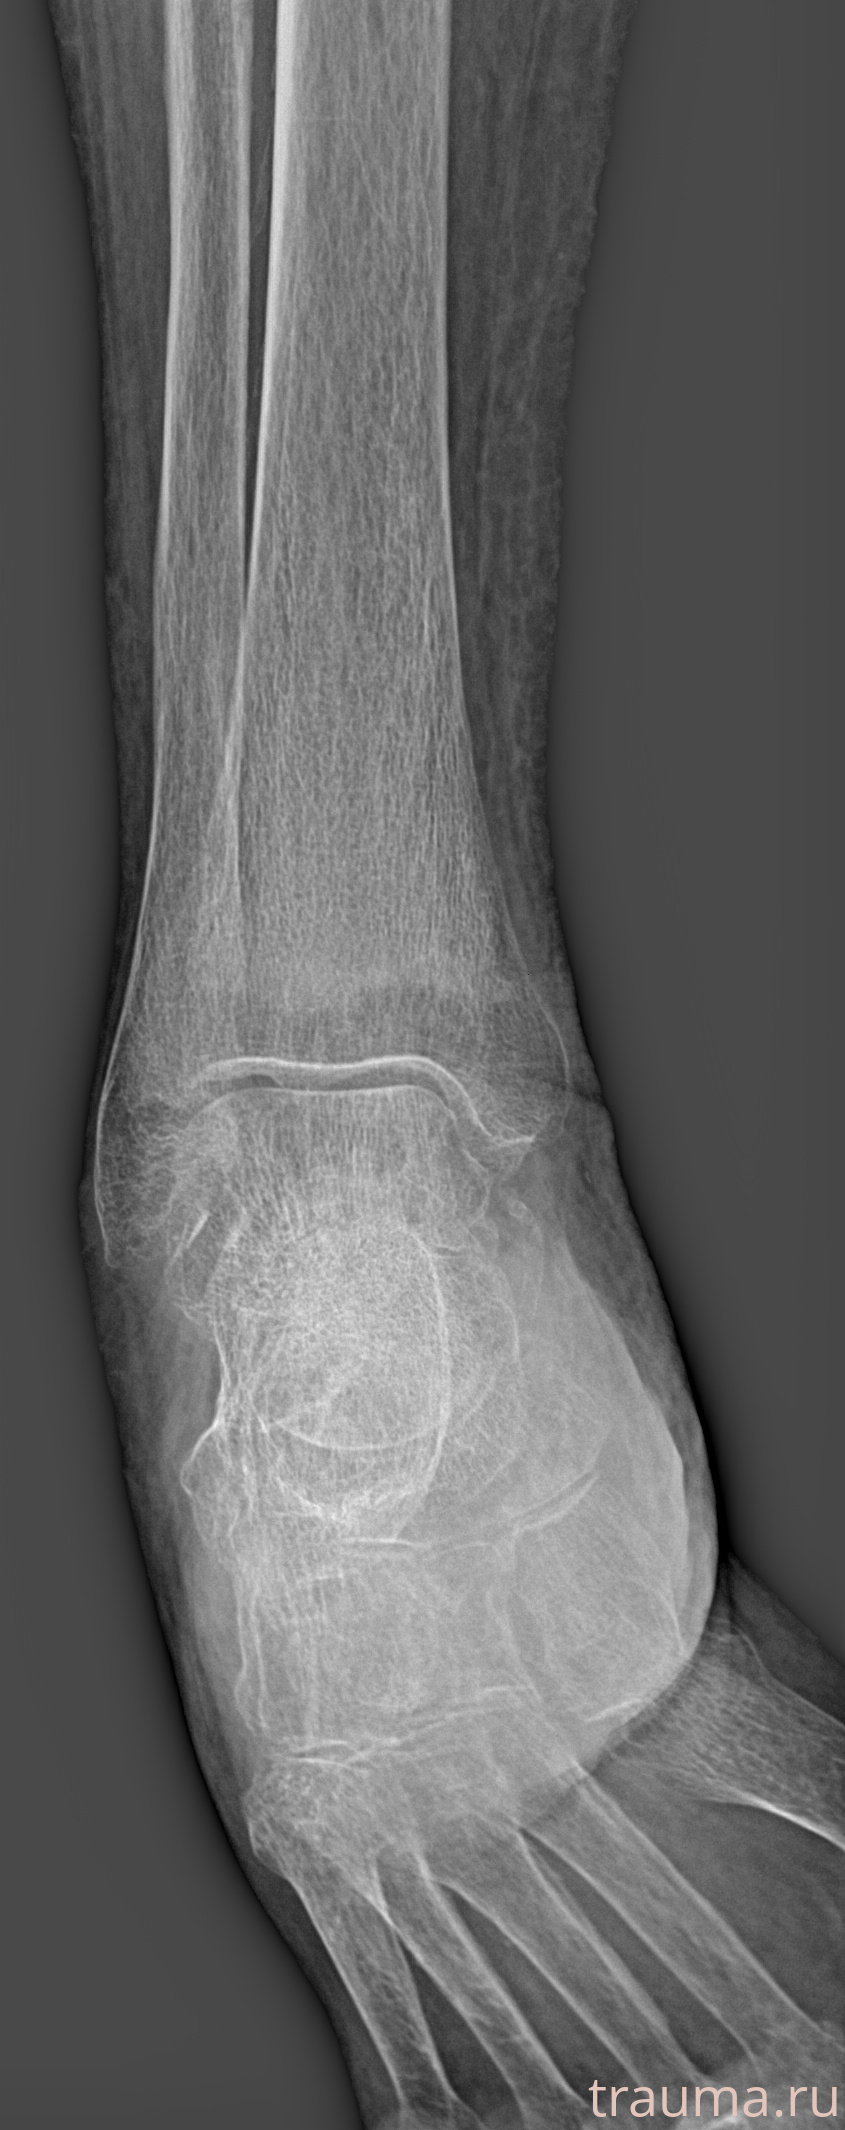

Рентгенограммы